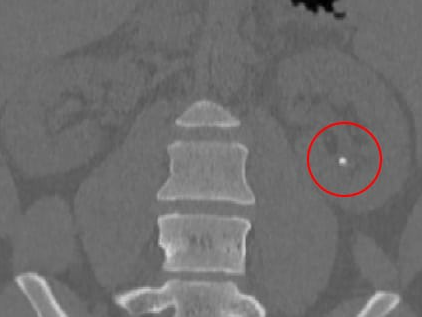

영상학적 검사에서 약 90%가 방사불투과성(radiopaque)으로 하얗게 X-ray 나 CT에서 관찰되며,

초음파, CT로 진단하게됩니다.